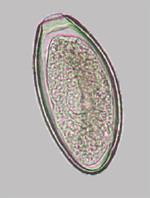

Describe the morphology of a Parascaris equorum egg.

Round and thick walled with undiff morula in the centre.